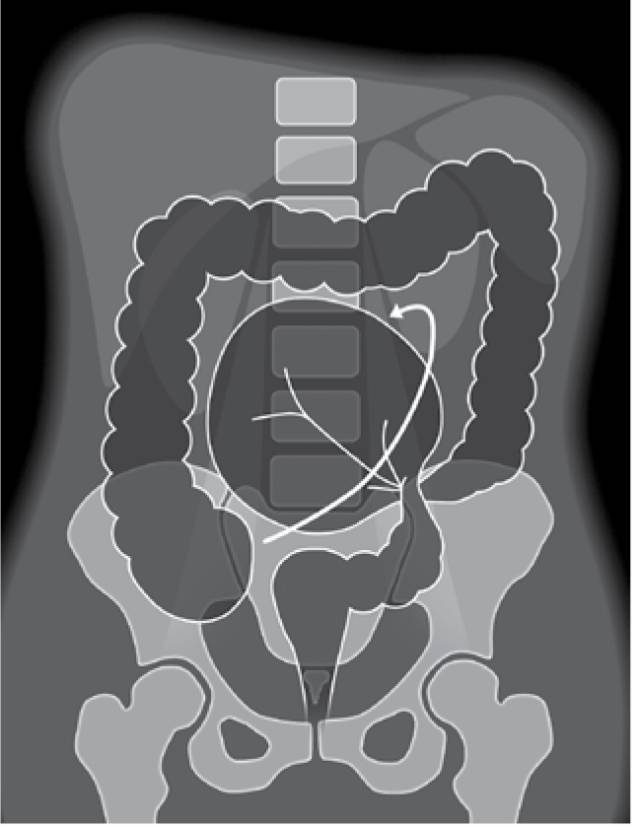

关于肠道扩张您可能不知道的诊断技巧

一位典型肠梗阻患者的x线平片,可以看到明显的扩张积气肠管.

肠袋缺失:当肠管明显扩张时,结肠袋变平致显示欠清.